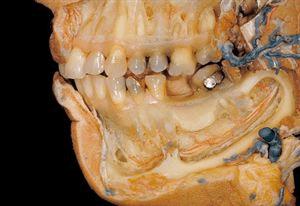

最详细解剖照片介绍和赏析

5.通过解剖切除颌周围骨骼的外层组织后,露出下颌牙和下巴上的血管以及感觉神经。拍摄这个解剖过程的速度非常缓慢,部分原因是因为柯达彩色胶卷必须送到纽约的柯达公司进行冲洗。格鲁伯还得检查冲洗出来的照片,他感到满意后,贝塞特才能继续解剖。